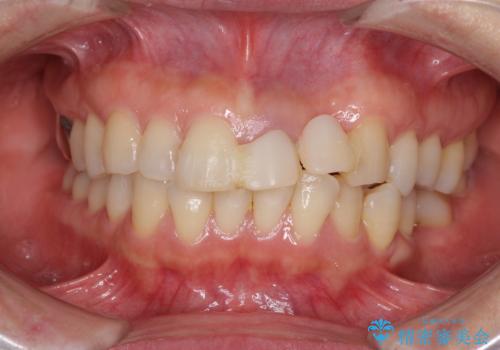

[ 矯正と補綴、総合歯科治療 ] クロスバイトを避ける前歯部審美ブリッジ

![[ 矯正と補綴、総合歯科治療 ] クロスバイトを避ける前歯部審美ブリッジの症例 治療前](https://seimitsushinbi.jp/wp/wp-content/uploads/2021/07/IMG_9914-500x350.jpg?v=1626697179)